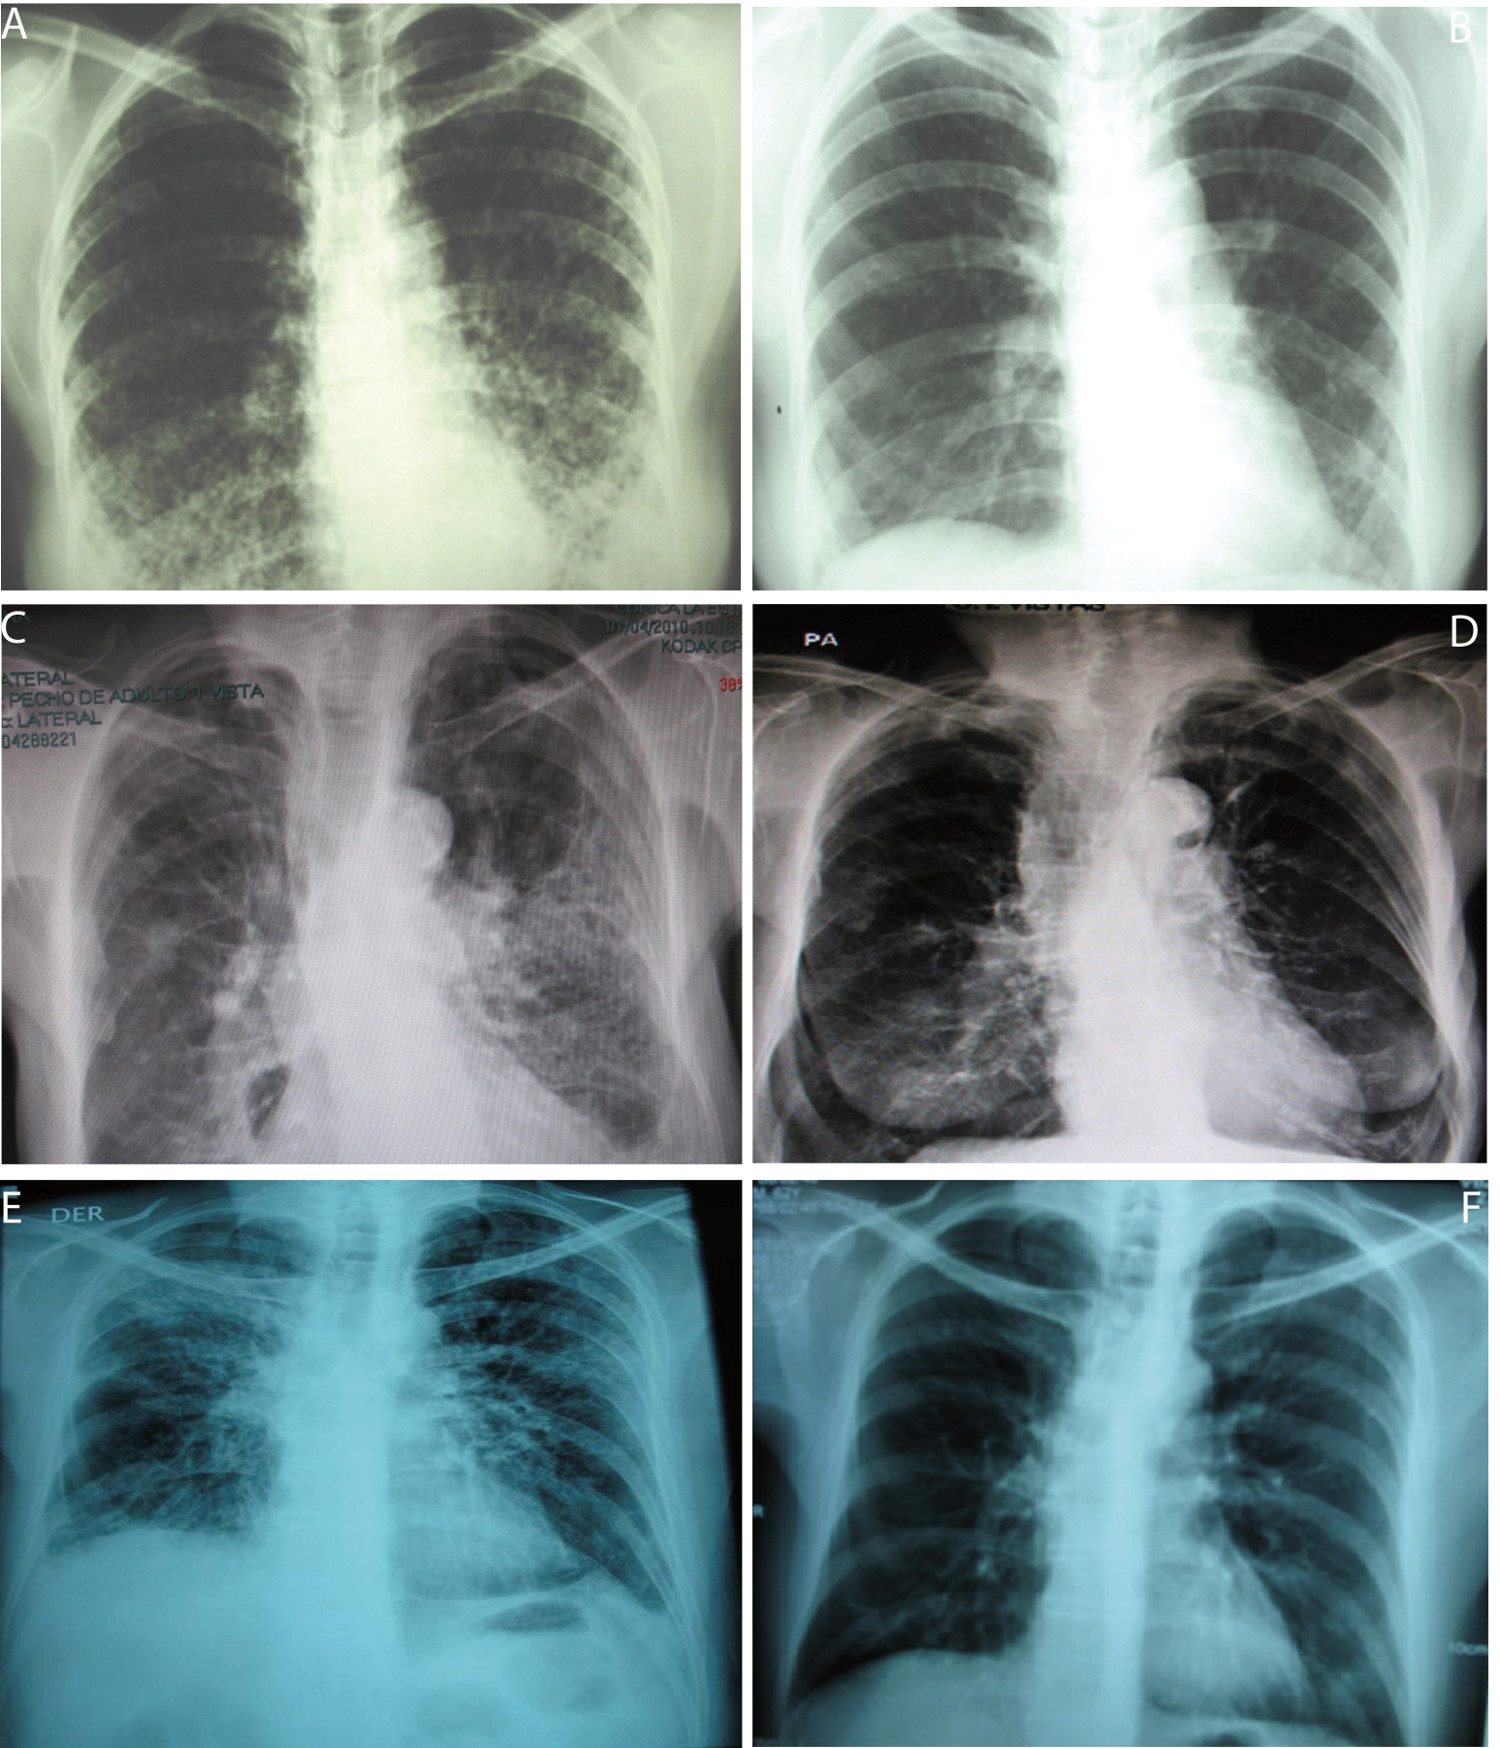

Figure 1

Chest X-ray of 3 patients. A and B: Chest X-ray of patient 1, December 2001 and July 2003 before and 22 months after ganciclovir treatment end, respectively. C and D: Chest X-ray of patient 5, April 2010 and September 2010, before and two months after ganciclovir-vaganciclovir treatment end, 4 months after trimethoprin sulfamethoxazole treatment end and 1 month after voriconazol treatment end, respectively. E and F: Chest X-ray of patient 6, November 2009 and February 2010, before and two months after trimethoprin sulfamethoxazole end and at ganciclovir treatment end, respectively.

A 38 year-old woman, heterosexual with no history of promiscuity, was admitted to a medical care hospital on January 21th, 2002 with a 3 month history of chills, fever and coughing with sputum production, progressive dyspnea, fatigue, weakness, anorexia and 10 kg weight loss. At the time of presentation she was being treated with 4 antituberculosis drugs for 34 days determined by bilateral reticulonodular interstitial infiltrates in her chest X-ray (Fig. 1A) and chest computed tomography (chest CT). Samples of bronchoalveolar lavage (BAL) were mycobacteria stain and culture negative. Transtracheal wash was fungus stain and culture negative too. She had a low level of hemoglobin (11.3 g/dL), hematocrit (37.7%), peripheral blood lymphocytes (699 /mm 3 ), CD4+ T cells/mm 3 92 (13.2%) and CD8+ T cells/mm 3 144 (Table 1 and Figure 2:A-C). Lung biopsy showed nonspecific focal, interstitial fibrosis, a few Pneumocystis jiroveci (P. jiroveci) and DNA of EBV by polymerase chain reaction (PCR). The patient's vital signs showed a temperature that ranged from 38 °C to 39.5 °C, respiratory rate of 40, pulse of 140, weight of 43 kg, height 1.62 m. Treatment with trimethoprin sulfamethoxazole and prednisone for 21 days was commenced on February 6th. The patient's temperature fell to 38 °C and pulse to 128, but she persisted tachypneic with a respiratory rate of 56 and coughing. Her weight decreased to 38 kg.

1657-9534-cm-43-04-00305-gt01

The result of serum antibodies of different viruses included CMV, EBV and HIV test are shown in Table 1. On April 16th, 2002, treatment with intravenous ganciclovir and 80,000U of interferon α sublingual every 8 h was commenced. Five days later her vital signs had improved with a respiratory rate of 36, pulse of 88 and weigh of 42 kg. One month after ganciclovir was commenced the lymphocytes count had risen to 3,148/mm 3 and CD4+ T cells count was 322 cells/mm 3 (10.2%) and CD8+ T cells count was 228 cells/mm 3 (Fig. 2:A-C). She was treated with ganciclovir for 5 months and INFα for 8 months. In June 2003, her weight was 60 kg, respiratory rate 20, pulse 80 and her chest X-ray had only minimum residual lesions in the lower lung lobes (Fig. 1B). On October 14th, 2010 the patient was asymptomatic and her lymphocytes count was 1,988/mm 3 , CD4+ T cells were 503/mm 3 (25.3%), with 684 CD8+ T cells/mm 3 . Also her CD4+/CD8+ T cells ratio was normal (Fig. 2: A-D).

A 74 year-old woman with history of osteoporosis, gastric cancer 30 years before, cigarette smoke exposure, chronic obstructive pulmonary disease with spontaneous pneumothorax 8 months before, was attended by Staphylococcus aureus methicillin sensitive bacteremia and pneumonia. She was treated since April 1st, 2010 with piperacillin-tazobactam and mechanical ventilation support. The hemograms of April 1st and 9th showed lymphocytopenia of 610 mm 3 and 450 mm 3 respectively. A chest CT showed findings of pulmonary thromboembolism, alveolar infiltrates in the left lung and interstitial fibrotic lesions, bulla, bilateral pleural effusion and right cardiomegaly (Fig. 1 C). On April 11th, she had 109 CD4+ T cells/mm 3 (17.9%) and 43 CD8+ T cells/mm 3 (Fig. 2: A-C). On April 9th she was treated with trimethoprin sulfamethoxazole for Stenotrophomonas maltophlia nosocomial pneumonia and empirical for P. jiroveci pneumonia. Predisone plus ganciclovir were added. The results of antibodies to different virus are in Table 1. On April 27th, her lymphocytes count increased to 730/mm 3 . On April 30th, she could be removed from mechanical ventilatory support. She was treated with valganciclovir for 3 months and voriconazole for 4 months, by repeated isolation of Aspergillus fumigatus in bronchial secretions without a lung biopsy because of the high risk of the procedure. In August she had an improvement in her immunology alterations which are shown in Table 1 and Figure 2: A-D. She also improved pulmonary infiltrates (Fig. 1: D).

A 62 year-old professor was diagnosed on November 7th, 2010 with coughing, adynamia, fatigue and progressive dyspnea for four months before. He had antecedents of amigdalectomy at 19 years old, hepatitis at 16 years old, appendectomy at 59 years old, red blood cells transfusion during diverticulitis with peritonitis in January 2006 and chronic renal diseases treated with hemodialysis until May 2007. Also he had a history of oral ulcers on two occasions in 2008 and urinary infection in January 2009. At the moment of medical examination, his chest X-ray showed diffuse bilateral interstitial infiltrates (Fig. 1E). The chest CT had reticular infiltrates greater in the right upper lung lobule, bronchiectasis, irregular interstitial subpleural thickening and ground-glass opacities superimposed. Previously, he had tuberculin test on 11 mm but the ZN smear mycobacterial and fungus culture of BAL and three ZN sputum were negative.

On November 17th, 2009, the lymphocytes count was 681/mm 3 , CD4+ T cells were 279 / mm 3 (40.9%) and CD8+ T cells were 110/mm 3 (Table 1 and Fig. 2: A-C). He had IgG and IgM anti CMV negative but CMV PP65 antigen positive Table 1. On November 22th, 2009 a induced sputum calcofluor stain showed structures compatible with P. jiroveci. On November 23rd, he was treated with prednisone and trimethoprin-sulfamethoxazole for 3 days followed by clindamycin and primaquine for 18 days. On November 26th, he started ganciclovir for 3 months. On December 17th the fever, cough, dyspnea, fatigue and weight loss had improved. On December 17th, 2009 the lymphocytes count was 957/mm 3, CD4+ T cells were 318/mm 3 (33.2%) and CD8+ T cells were 182/mm 3 . The improvement of different immunology alterations, after gancicolvir treatment, can be seen in Table 1 and Fig.2:A-D. The radiology pulmonary infiltrates improvement can be seen in the Fig.1: F.